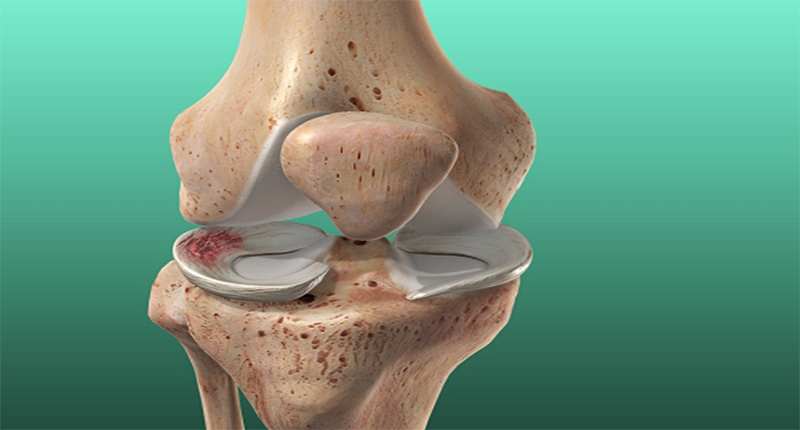

Sụn chêm nằm ở đầu gối, thuộc dạng sụn xơ có dạng giống chữ C. Mỗi đầu gối có hai sụn chêm, nằm ở giữa đầu xương đùi và xương chày.

Chức năng chính của sụn chêm là đón nhận những áp lực cho va đập vào đầu gối và là một lớp mềm ngăn cách giữa xương của khớp gối. Tổn thương sụn chêm khớp gối thường gặp nhất là đứt rách sụn chêm gây hạn chế vận động và đau đớn.